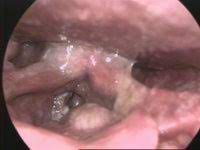

This picture gallery contains some examples of the more common. The larynx is your voice box. For instance, if you have cancer of larynx, it may look like red patches but with an irregular surface. Hpv has been linked to cancer that affects the soft palate, tonsils, back of the tongue, and the side and back wall of the throat. Nearly all skin cancers can be treated effectively if they are found early, so knowing what to look for is important. Once the t, n and m scores have been assigned, one of these overall stages is assigned: Imaging tests, such as computed tomography, magnetic resonance imaging, and positron emission tomography, are used to determine the size of the cancer and how far the cancer has spread. The following are some characteristic features of how mouth cancers look for people wondering what does mouth cancer look like. Mouth and throat cancers may look like open sores, growths, or discolored areas in the mouth. Chandrasoma takes us on a tour to show the visual symptoms of esophageal cancer and the damage that can develop to the lining of the esophagus. In some types of throat cancer, such as cancer of the larynx, visible early cancer symptoms can be observed during a medical examination. This cancer is often silent and does not cause symptoms until very late. Mouth cancer can appear on the lips or anywhere in the mouth, including the tissues inside the cheeks, the tongue, and the gums.

Throat Cancer Wetin Be Di Causes And Signs Of Throat Cancer Bbc News Pidgin from ichef.bbci.co.uk I had an on and off sore throat and hoarseness for many many months, but was a smoker, so didn't think too much about it. The sensation of a lump in the throat is called globus. Imaging tests, such as computed tomography, magnetic resonance imaging, and positron emission tomography, are used to determine the size of the cancer and how far the cancer has spread. They may look like a patch or a lump or look like an ulcer. Throat cancer will start with initial symptoms such as a coughing. It shows that the oral cancer that had been present in the throat or the back of the tongue has metastasized into one of the lymph nodes present in the neck. The pictures shown below are from four patients with squamous cell carcinoma of the supraglottis (top part of the voice box). In some types of throat cancer, such as cancer of the larynx, visible early cancer symptoms can be observed during a medical examination.

This includes a typical visible red patch with an irregular surface on the voice box.

Often the patient will present with a neck node. Tobacco use, whether smoking or chewing, can also lead to cancer of the lips (as well as other mouth cancers). The larynx is your voice box. It may be numb or firm to feel and doesn't fade away over time. This includes a typical visible red patch with an irregular surface on the voice box. Cancer of the larynx is often grouped into early (stage i), intermediate (stage ii) or advanced (stages iii & iv) disease groups. Human papillomavirus (hpv) is a common sexually transmitted infection that increases the risk of certain types of throat cancer. Oropharyngeal cancer is a type of head and neck cancer in which cancer cells are found within an area of your throat called your oropharynx. It often causes changes in patches of skin, such as thick growths or. The most common symptom of thyroid cancer is a hard lump on the neck—but most patients experience no symptoms at all. Hoarseness, trouble swallowing, and a visible lump in your neck are among the symptoms of. The skin may feel thicker or. The outlook depends, to some extent, on where cancer starts.